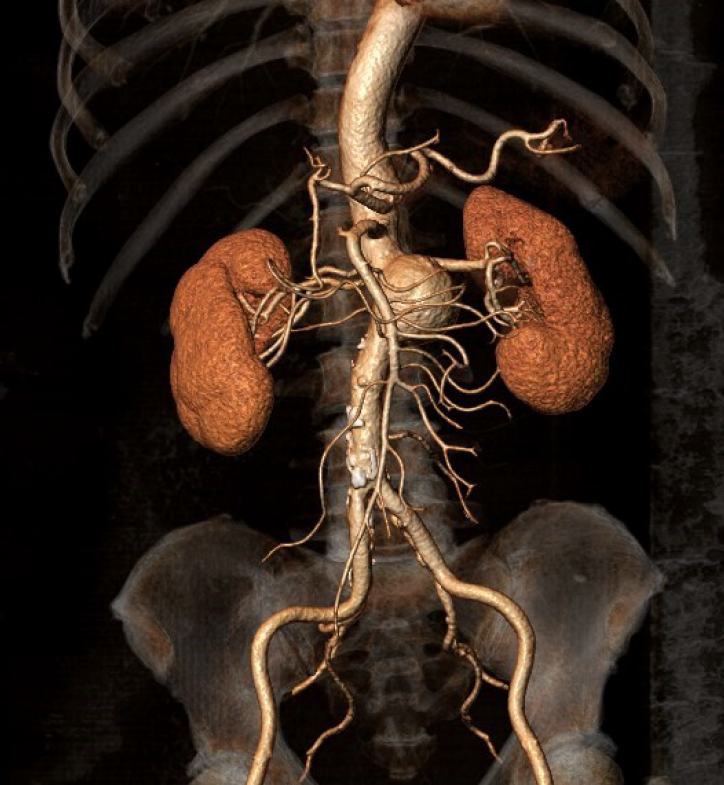

▲患者腹主动脉3D重建图

治疗困难重重!该患者腹主动脉瘤位置离双侧肾动脉不足1cm,离肠系膜上动脉距离不足2cm,且右肾动脉有2个分支。按传统介入治疗方法,必将把双侧肾动脉隔绝,甚至会影响肠系膜上动脉血流,造成肾及小肠缺血坏死。